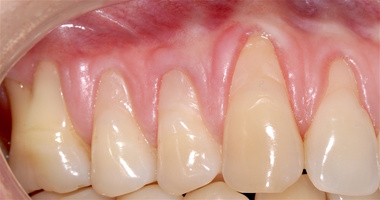

Во всех случаях применения аутотрансплантата и ТМО (dura mater) наблюдается сопоставимый положительный клинический результат по всем параметрам оценки рецессий десны (табл. 4). В случае нескольких зубов в области наиболее глубоких рецессий с наименьшими клиническими показателями имеет место сохранение класса рецессии не более первого класса (9 зубов) и глубиной не более 2 мм, 1.6 зуб — 3 мм.

В зарубежной литературе встречается также совокупный показатель эффективности лечения рецессий десны — процент закрытия корня зуба — отношение разница между конечным и исходным значениями глубины рецессии к исходному значению в процентах. Положительный результатом лечения является значение равное или более 80% [4]. Использование только показателя глубины рецессии десны для анализа эффективности лечения без учета остальных показателей (ТКД, ШКД, РРД, ЗДК) не дает полной картины результата и может быть применимо только в совокупности с другими показателями (рис. 6а-й).

Так в нашем случае процент закрытия корня зуба наблюдается больше 80% у 13 зубов. Менее 80% — у 11 зубов. Это связано с сохранением класса рецессии после лечения в области зубов с наибольшим классом рецессии и наибольшим показателем глубины рецессии. При этом средний показатель всех 24-х оперированных зубов — 83,1%. При этом среднее значение процента закрытия корня зуба для зубов с положительным результатом (более 80%) составляет 96,65%. Среднее значение для результатов менее 80% — 54,73, что связано с изменением глубины рецессий с 6 мм до 3 мм, с 4 мм до 2 мм и с 2 до 1 мм. При этом для аутотрансплантата и для ТМО результаты сопоставимы.

Через 12 месяцев (рис. 7а-г) на срезах компьютерной томограммы 11-ый и 13-ый зубы находятся в костной ткани, при этом костные пики и перегородки укрепились, объем их увеличился; вестибулярно заметен объем костной массы, предположительно компактной формации, исходя из электронной плотности участка. Этим объясняется отсутствие рецидива при лечении рецессии десны как в случае применения аутотрансплантата, также и ТМО (dura mater).